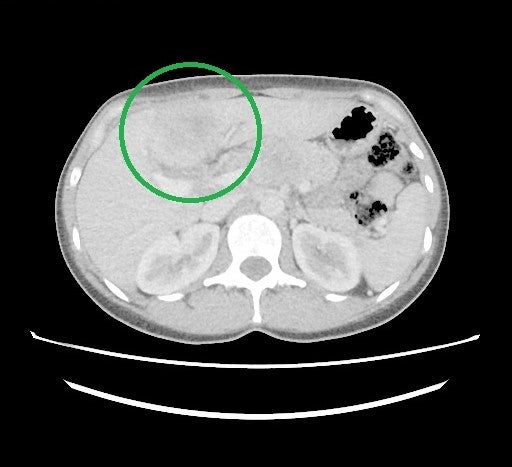

3-4/2025 CT staging – susp. cholangiokarcinom v terénu PSC s lymfadenopatií

Obr. 2: Stejné ložisko v CT obraze